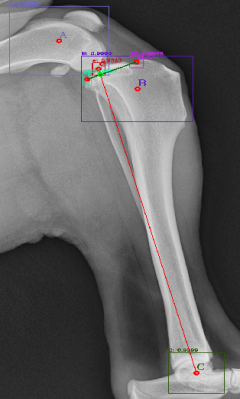

Following the identification of points of interests, and drawing of the lines of interest, i.e. the Functional Tibial Line (FTL) and the Medial Tibial Plateau Line (MTPL), another line is drawn such that the relation of new line and the FTL is 90°. Tibial plateau angle is the angle between this new line and the MTPL; this is shown in Fig. 3.

Most of the source dataset of over a thousand unique knee radiographs were distorted, had poor patient positioning, or were otherwise unfit for annotating. 250 of the original images were of sufficient quality to contribute to this effort. These images were set to have 6 different classes for training purposes, as mentioned and shown in Fig. 4. These were then trained using YOLOv3 [10] and the results of the predicted annotations are shown in Table I. From these predictions the centroids were extracted, which is then used to plot the FTL and MTPL. Then using the method mentioned in Section II, TPA is calculated. Examples of images, the region of interests detection and their respective TPA determination is shown in Fig. 6 and Table I: